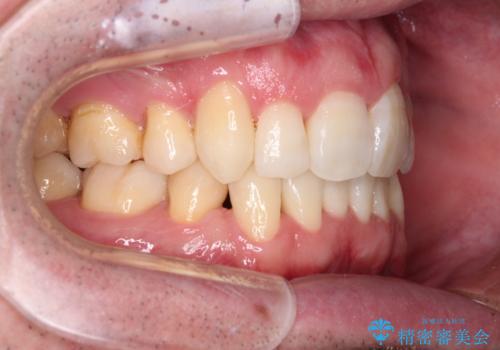

- 前歯のデコボコを気にして来院された患者様です。

叢生の解消とともに、前方に張り出した上顎前歯を引っ込めることを目的とし、上下左右の第一小臼歯4歯を抜歯をしてワイヤー矯正により治療することとしました。

治療開始直後は、あっという間に歯列が整い、すぐに終わるのではないかと思われましたが、治療の後半にブラックトライアングル解消のための処置を行ったため、当初予定していた2年半ほどの期間を要することとなりました。